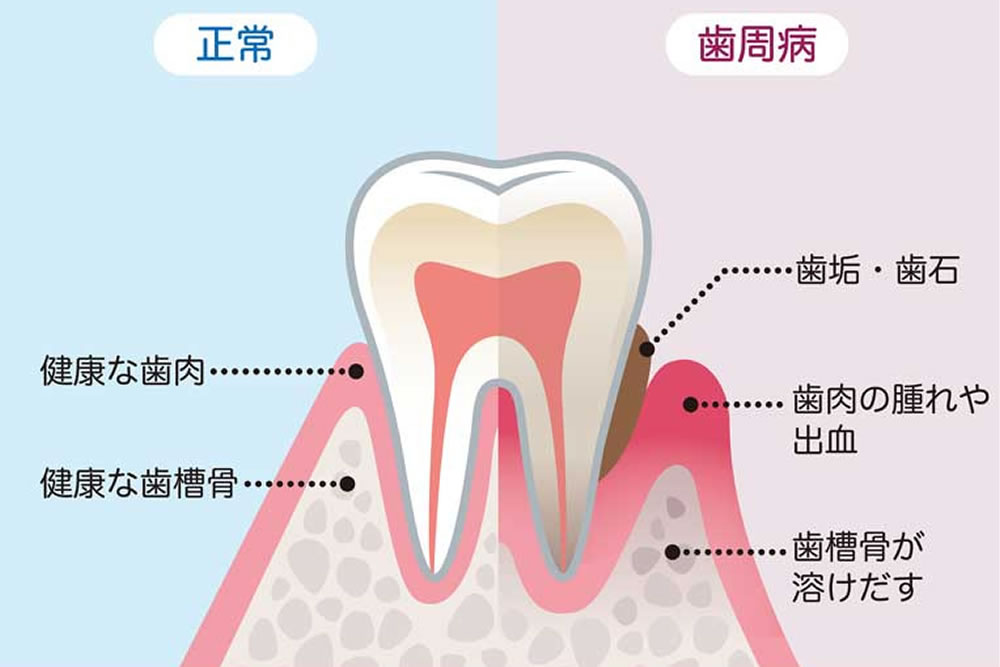

歯周病は自覚症状がほとんどなく進行するため、重症化しやすいという特徴があります。また、症状の悪化には生活習慣なども関係し、汚れの蓄積や細菌の繁殖は日々起こっているため、治療期間中に歯周病が悪化する可能性もゼロではありません。短期治療によって、口腔ケアや歯周病治療を集中して行うことによって症状の早期改善・緩和が期待できます。

歯周病治療との併用

歯周病に罹患している状態でインプラント治療を行うと、手術後にインプラント周囲炎(インプラントの歯周病)を引き起こす可能性が高くなります。

歯周病に罹患している状態でインプラント治療を行うと、手術後にインプラント周囲炎(インプラントの歯周病)を引き起こす可能性が高くなります。

インプラント周囲炎が悪化すると、インプラント周辺の歯茎や歯槽骨が溶かされ、最終的にインプラントが抜け落ちてしまいます。

当院ではインプラントを長く良い状態で維持していただけるよう、インプラント治療の事前検査等で歯周病が確認できた場合には、歯周病治療を優先して行います。